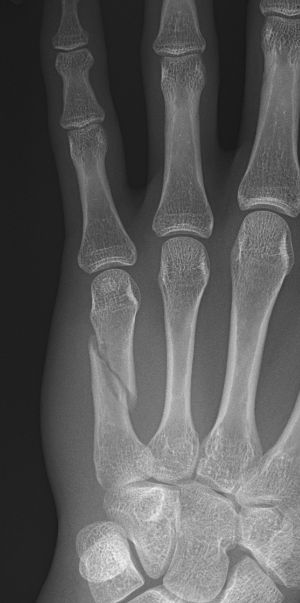

Tenneb-fraktur = omvänd bennettfraktur: intraartikulär fraktur i basen av metakarpale 5, volart-radialt fragment ligger på plats medan ECU-senan (extensor carpi ulnaris) drar distala fragmentet ulnart-proximalt.